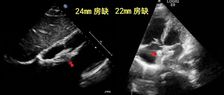

近期,沈阳医学院附属第二医院马晶茹教授团队成功应用MemoLefort左心耳封堵器,为一名71岁高龄房颤患者完成完成“射频消融+左心耳封堵”一站式手术。由于该病例心耳位置较低,术者选择房间隔低位穿刺,满足更好轴向,避免心耳上缘压迫,后通过DSA与ICE精准指引,利用MemoLefort封堵器的贴壁成角倒刺设计实现稳固锚定与严密封堵。